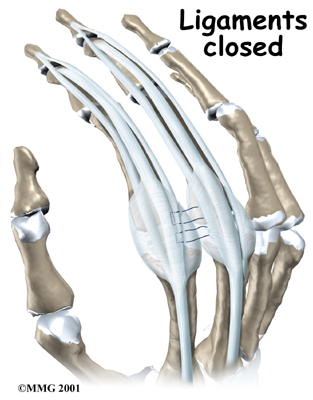

When the new joint is in place, the surgeon wraps the joint with a strip of nearby ligament to form a tight sac. This gives the new implant some added protection and stability.

The soft tissues are sewn together, and the finger is splinted and bandaged.